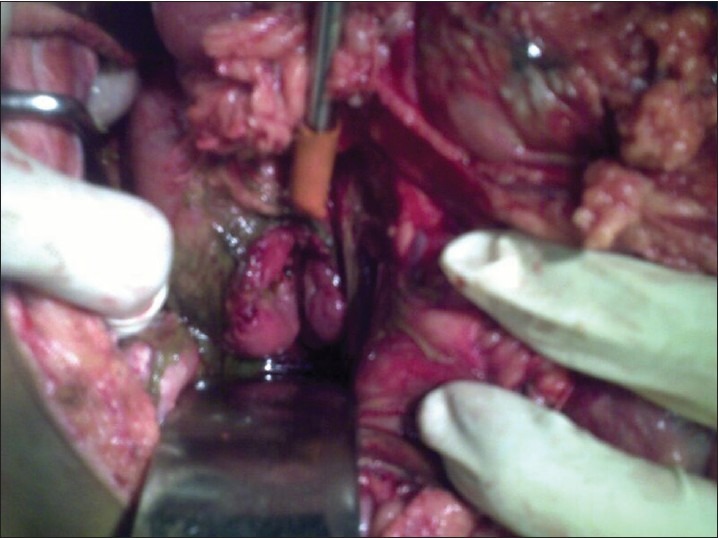

With the inventions of faster cars and even more faster motorbikes there is a worldwide increase in road traffic accidents, which has increased the incidence of blunt abdominal trauma but still duodenal injury following a blunt abdominal trauma is uncommon and can pose a formidable challenge to the surgeon and failure to manage it properly can result in devastating results. It may typically occur in isolation or with pancreatic injury. Here, we report a case of an isolated transection of the third part of the duodenum with normal pancreas following a blunt abdominal trauma. The initial clinical changes in isolated duodenal injury may be extremely subtle before life-threatening, peritonitis develops. Hence, a high index of suspicion, on the basis of mechanism of injury and physical examination is the key in early detection of duodenal injury especially in a rural hospital like ours where the facilities for computed tomography scan are not available.